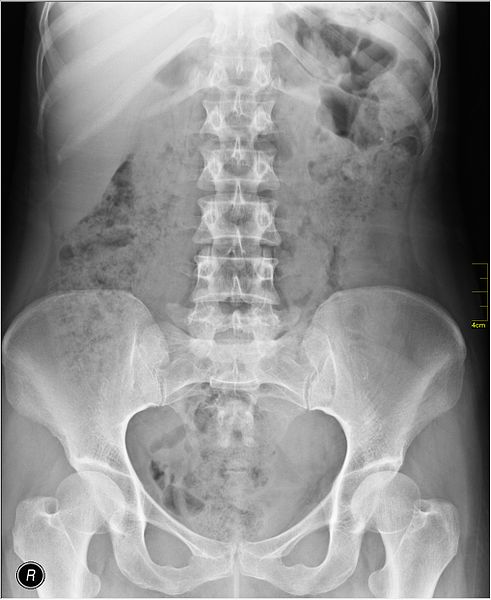

It is not uncommon, when seeking care from a chiropractor, to receive X-rays of the back. X-rays are a key component of the chiropractic practice. (1)

It is not surprising that routine X rays from chiropractors, that deliver radiation to the patient, do not fall under the category of a "wise choice." Because X rays are a routine part of chiropractic care, the ICA has issued a response to the idea of choosing wisely - "ICA Recognizes Radiographic Studies Are the Standard of Practice in Chiropractic" - that encourages chiropractors to "raise their voice and be heard."

One problem with this stance is that X rays use electromagnetic radiation that penetrates soft tissue and does not capture it on film. Therefore, an X-ray will typically not show any abnormalities involving ligaments - including herniated discs, bulging discs, sciatica, pinched nerves or disorders affecting the spinal cord.